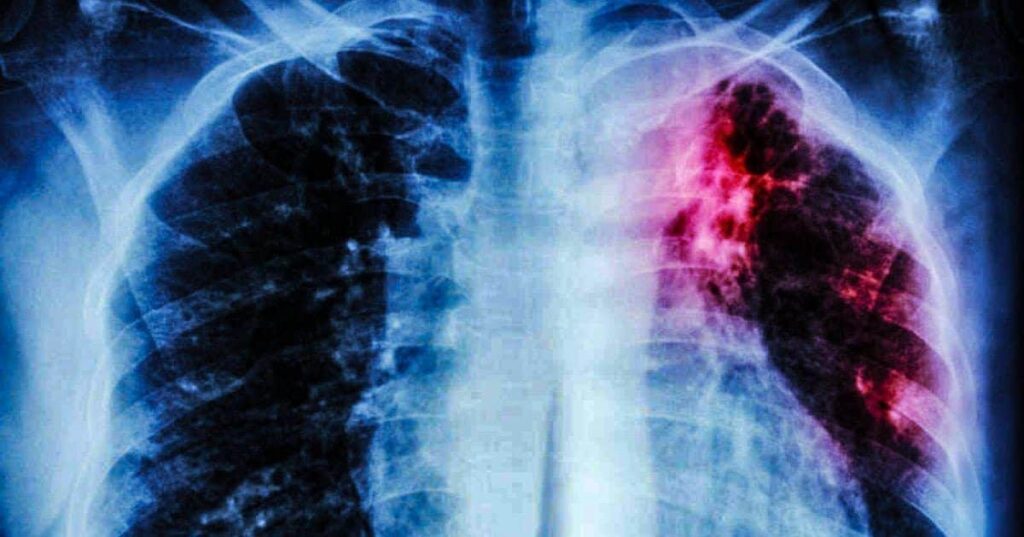

En este sentido, destacó que el lema de este año es “Invirtamos en poner fin a la tuberculosis. Salvemos vidas”, y que “es causada por la bacteria tuberculosis y es curable. En unidades médicas se realizan las pruebas de baciloscopia y se brinda tratamiento por seis meses en los pacientes”, añadió.

Nava Uscanga explicó que en caso de presentar: tos intensa por más de tres semanas y con sangre o flemas, dolor de pecho, fiebre, escalofríos, sudores nocturnos, falta de apetito, pérdida de peso, debilidad o fatiga, acudir al centro de salud o ingresar a saludparatodos.ssm.gob.mx para recibir atención médica.